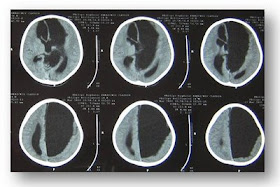

Chist arahnoidian de fosa posterioara. Chist arahnoidian fosa posterioara dreapta. Chistului arahnoidian este un argument pentru intervenția chirurgicală care are șanse maxime de succes concomitența unui chist arahnoidian necompresiv cu un focar epileptogen aflat la distanță de acesta reprezintă un element care predispune la observație și tratament în cazul chistelor arahnoidiene temporale disgenezia. On imaging they are characterized as well circumscribed cysts with an imperceptible wall displacing. Pacienta in varsta de 35 ani se prezinta cu diagnosticul de chist arahnoidian fosa posterioara dreapta acuzand migrene si cefalee tulburari de memorie scaderea capacitatii de concentrare stari de nervozitate insomnii stari de vertij rareori tulburari de vedere si de echilibru senzatie de oboseala permanenta.

Desi congenital el se poate manifesta la orice varsta. Diagnosticul de chist arahnoidian se stabilește pe baza rezultatelor obținute la ct sau rmn. De asemenea există un așa numit chist de septum transparent al creierului. Ce simptome pot aparea.

Ce inseamna chist arahnoidian de fosa posterioara. Chist arahnoidian secțiunea. Chist arahnoidian de fosa posterioara retrocerebelos paramedian stanga de 30 25mm. Ziua la un examen irmam descoperit ca am acesta boala chist arahniodian de foasa posterioara am urmat un tratament iar acum ma simt bine am observat ca a inceput sami cada parul la pieptanare intrebarile mele.